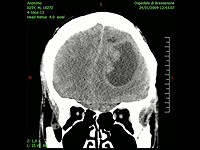

Израильские ученые предложили новый подход к лечению рака мозга

Ученые из Института Вейцмана обнаружили бактериальные сообщества в опухолях мозга. Бактерии влияют на устойчивость к терапии и их подавление может улучшить прогноз заболевания.

Менее 5% пациентов с диагнозом глиобластома живут 5 лет и дольше, поэтому борьба с этим онкологическим заболеванием является одним из важных приоритетов ученых. Мозг долгое время считался стерильной средой, защищенной гематоэнцефалическим барьером от проникновения патогенов. Но новое исследование показало, что различные бактерии успешно преодолевают эту защиту и обитают внутри опухолей мозга. Работа опубликована в журнале Nature Cancer.

Ученые проанализировали 322 образца глиобластом и метастазов в мозге. Исследователи обнаружили бактерии как внутри опухолей, так и среди окружающих опухоль иммунных клеток. Метастазы оказались даже богаче бактериями, чем первичные опухоли – они содержали большее количество и разнообразие микроорганизмов.

Особенно важным открытием стало установление связи между бактериальным составом опухолей и выживаемостью пациентов. У больных, проживших менее года, обнаружились более богатые бактериальные сообщества, чем у тех, кто прожил более двух лет. Эксперименты показали, что выделения некоторых бактерий, например рода Bacillus, делают раковые клетки устойчивыми к химиотерапии темозоломидом.

"Глиобластома – это очень агрессивная злокачественная опухоль головного мозга, и даже после таких методов лечения, как хирургическое вмешательство, лучевая терапия, химиотерапия и биологическая терапия, продолжительность жизни остается очень ограниченной, – говорит соавтор работы профессор Шломит Юст-Кац, – Обнаружение бактерий в опухолях открывает путь для будущих исследований роли этих бактерий в развитии заболевания и дает надежду на поиск новых методов помощи пациентам".

Результаты работы открывают новые перспективы для разработки направленных методов лечения рака мозга с учетом найденного бактериального фактора.